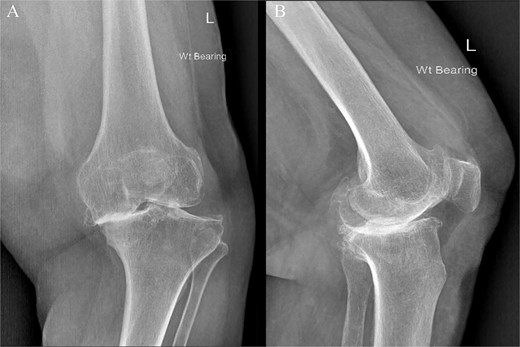

An 80-year-old woman presented with severe left knee pain, disability, and recurrent swelling. X-rays showed advanced osteoarthritis (Kellgren-Lawrence stage IV) with joint space narrowing, varus deformity, and a large medial tibial plateau defect (Fig. 1). The potential bone defect on the medial plateau, which could result in an unsupported region of the tibial component, was identified and highlighted in orange on the pre-operative templating plan. Additionally, a 15.5° varus deformity in the alignment of the native knee was observed (Fig. 2). Patient-specific, 3D-printed surgical guides (Zimmer Biomet), created from MRI-based models, were used for precise femoral and tibial resections.

Preoperative face (A) and profile (B) X-rays showing end-stage knee arthritis with varus deformity and severe collision between the medial femoral and tibial condyles.